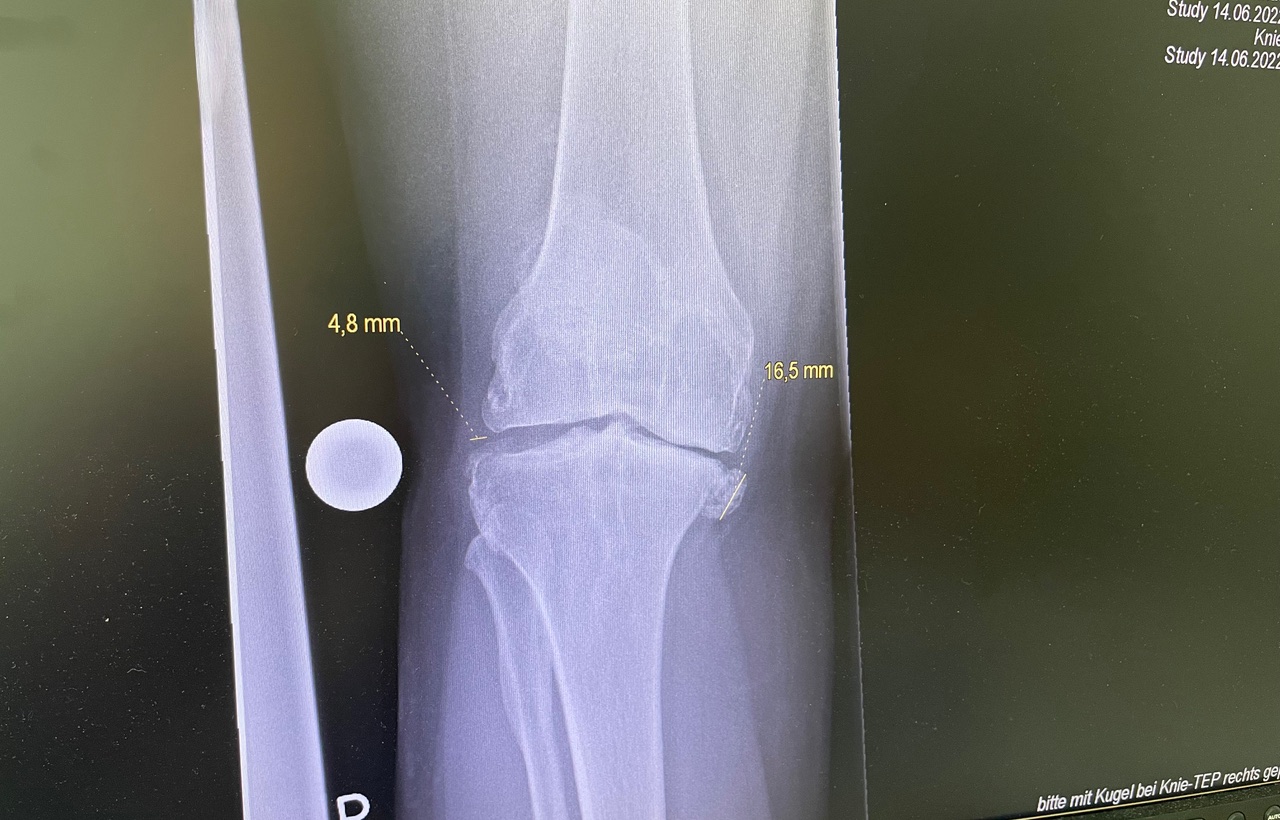

Η ολική αρθροπλαστική γόνατος είναι χειρουργική επέμβαση κατά την οποία αντικαθίσταται η φθαρμένη άρθρωση του γόνατος με τεχνητά εμφυτεύματα.

Πότε ενδείκνυται

Η επέμβαση προτείνεται όταν ο πόνος και ο περιορισμός της κίνησης δεν αντιμετωπίζονται πλέον με συντηρητική αγωγή.

• Οστεοαρθρίτιδα γόνατος

• Μετατραυματική αρθρίτιδα

• Σοβαρές παραμορφώσεις του γόνατος

Η επιλογή της τεχνικής και της πρόθεσης γίνεται εξατομικευμένα, λαμβάνοντας υπόψη:

• την ανατομία του γόνατος

• τον βαθμό φθοράς

Στόχος είναι η σωστή ευθυγράμμιση, η σταθερότητα και το φυσικό εύρος κίνησης.